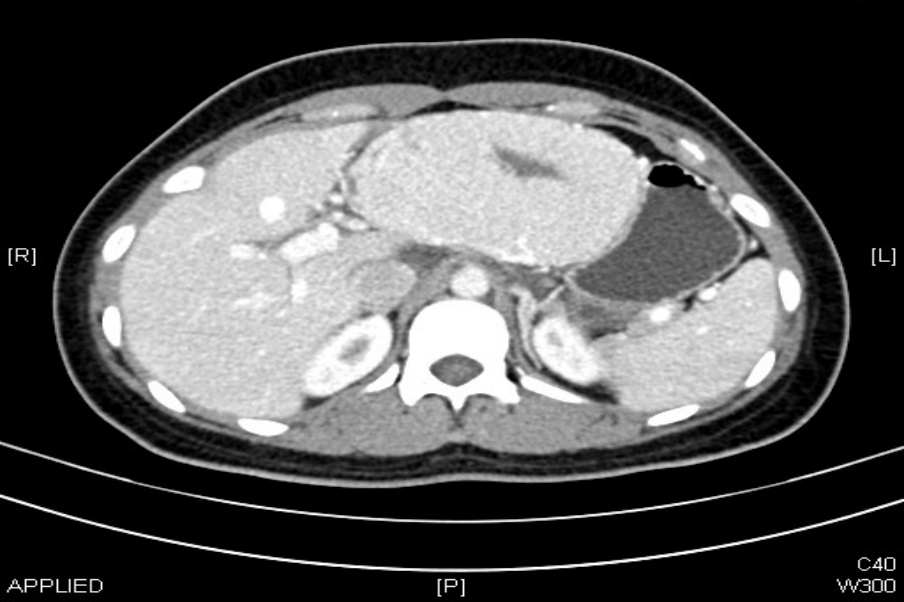

体检后发现左肝

居然长出了一个“大疙瘩”

直径约11cm

进一步检查后

确诊为肝局灶性结节性增生